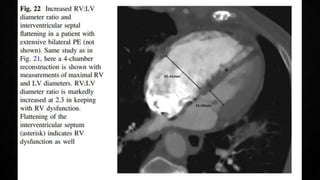

• Manifestations of RV pressure overload and dysfunction

• RV dilatation seen in >25% of patients with PE on TTE and is useful for risk stratification

ECHOCARDIOGRAPHY IN PE •Manifestations of RV pressure overload and dysfunction • RV dilatation seen in >25% of patients with PE on TTE and is useful for risk stratification of the disease • 60/60 Sign : combination of a pulmonary ejection acceleration time (measured in the RV outflow tract) of <60ms AND a peak systolic tricuspid valve gradient of <60mmHg • McConnell’s sign : depressed contractility of the RV free wall when compared to the RV apex • Finding present only in 12-20% of unselected PE patients • Decreased tricuspid annular systolic plane excursion (TAPSE) may also be seen in PE • Mobile right heart thrombi (in up to 18% of PE in the ICU) essentially confirm the diagnosis of PE and associated with high mortality rates